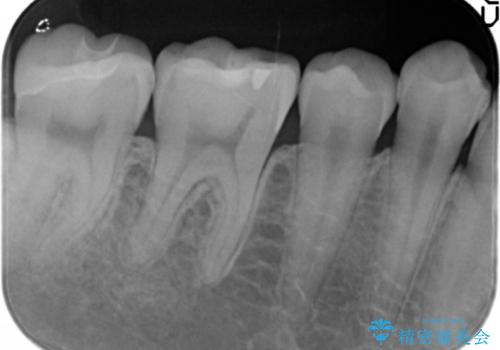

気にされていたフロスをした時のにおいがなくなり、喜んで頂けました。

治療終了後半年のメンテナンス時には「咬み合わせもばっちりです!」とおっしゃって下さいました。

インレーの種類:セラミックインレー e-max press